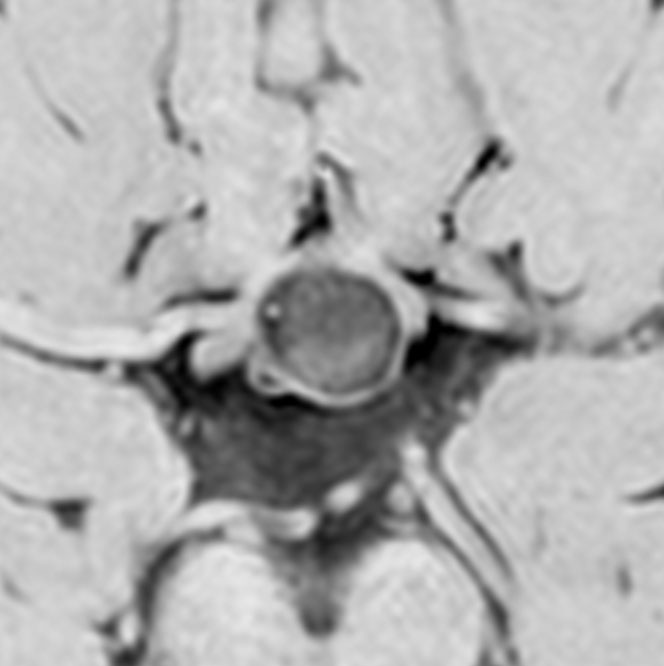

増大しても下垂体症状を出さなかった例

9歳の女の子に偶然発見された腫瘍です。何の症状もありませんでした。頭蓋咽頭腫と診断されて経過観察となりました。1年半観察しましたが腫瘍は増大して,視交差の変形が増して両耳側1/4半盲となり症候性となりました。下垂体機能は正常でした。

上のT2強調画像では,全体的に低信号で,高信号の部分が混在します。上右のCISS画像では,下垂体組織が右に変移していることが推定されます。

左がT1強調画像で高信号,右がT1ガドリニウム増強像ですが腫瘍は増強されません。正常か錐体が腫瘍の右側にくっついていて,ガドリニウム増強されています。典型的なトルコ鞍部黄色肉芽腫です。画像診断で,下垂体腺腫の腫瘍内出血とよく間違われるのですが,高信号になるのはコレステリン結晶を豊富に含むからです。ガドリニウム増強される部分がほとんどないという所見が頭蓋咽頭腫とは異なるところでしょう。